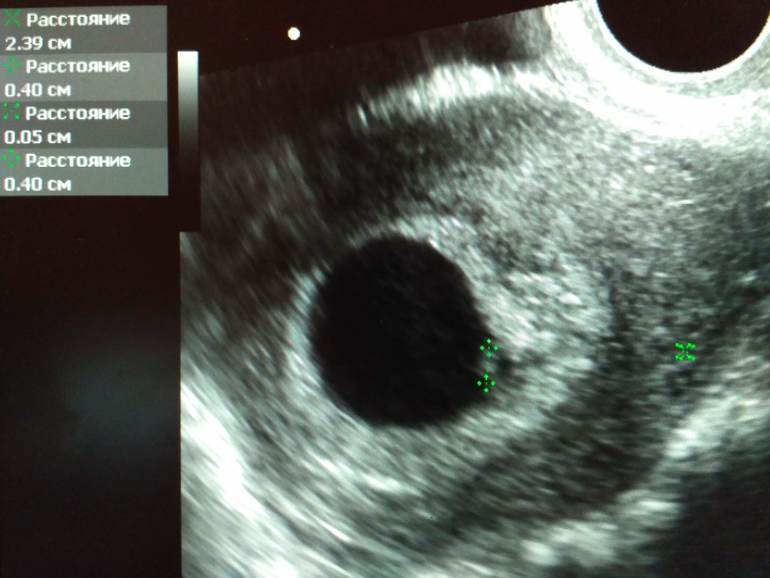

УЗИ 6+5

УЗИ, КТГ, доплерВчера наконец-то попала на УЗИ. Хотела раньше, но не получалось. А теперь думаю, что хорошо, что не получалось- раньше могли и сердечко наверное не услышать... Такая манюня у меня там оказалась.

Пока переживаний только добавилось, т.к. и плодное яйцо и хорион вроде моему сроку соответствуют, а вот эмбриончик совсем малюсенький - ктр 4,2мм. Я ожидала, что больше будет, тем более, что ХГЧ рос очень быстро, и цифры были высокие...Думала, что наоборот опережает немного срок, а оказалось отстает...:(

УЗИстка поставила срок 6 недель и сказала прийти еще через две недели.

Смутило, что соответствует 6 неделям, а у меня 6+5... Но да- надеюсь, что догоним еще. Главное, что сердечко бьётся:)